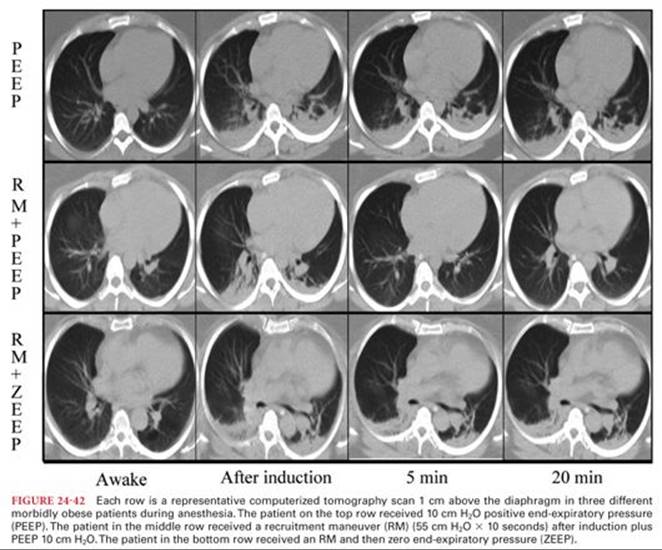

The key to understanding the complex changes which develop in the respiratory system during anesthesia is to appreciate the relationship between FRC and closing capacity (CC). CC is the sum of closing volume (CV) and RV. CV is the lung volume below which small airways begin to close (or at least cease to contribute expiratory gas) during expiration. Closure of small airways in the basal portions of the lung during deep expiration is a normal phenomenon due to the gravity-dependent increase in pleural pressure at the bases and due to the lack of parenchymal support in distal airways. CV and CC are not commonly measured in the pulmonary function lab. Measurement is either by a wash-in technique with a small bolus of an insoluble tracer gas such as 133Xe slowly inhaled then exhaled from RV (Fig. 24-21) or by nitrogen washout after inspiration of a breath of oxygen from RV. Normal values for CC in seated healthy young adults are 15% to 20% of vital capacity (VC).5 CC increases with age due to loss of structural parenchymal support tissue in the lung and an increase in RV. FRC increases slightly with age but the increase is greater for CC (Fig. 24-22).16 CC changes very slowly over time. However, FRC changes on a minute-to-minute basis as the mechanical advantage of the two springs (lung and chest wall) which determine it change. CC exceeds FRC in the supine position at age 45 and in the upright position by age 65. During anesthesia, a decrease in the elastic recoil of the chest wall due to the muscle-relaxing effects of almost all general anesthetics (with the possible exception of ketamine) and neuromuscular blockers causes FRC to decrease and it will often fall below CC.17 Similarly, an increase in elastic recoil of the lung due to fluid retention in the pulmonary parenchyma will lower the FRC. When an alveolar unit falls below its CC, even for a brief period during one respiratory cycle, the concentration of oxygen (PAO2) in that unit falls slightly. This results in the increase of venoarterial admixture (“shunt”; see the following text) and decrease in arterial oxygen tension (PaO2) seen in the elderly and during general anesthesia. When a region of the lung is kept below its CC, the loss in volume will eventually lead to atelectasis (Fig. 24-23) as the gas trapped in the alveoli is absorbed. A large part of the anesthesiologist’s job in the perioperative period is restoring the balance between FRC and CC. Because CC cannot be changed, this involves improving FRC by a variety of techniques to improve the mechanical advantage of the chest wall. These techniques may include ensuring adequate reversal of neuromuscular blockers, upright positioning, regional analgesia and possibly the use of positive end-expiratory pressure (PEEP) or continuous positive airway pressure (CPAP). The physiologic differences between PEEP and CPAP are subtle. However, by common usage, when positive pressure is applied during expiration to the airway of a patient who is having positive pressure ventilation, this applied airway pressure is referred to as PEEP. When a patient is breathing spontaneously, an applied airway pressure is referred to as CPAP.